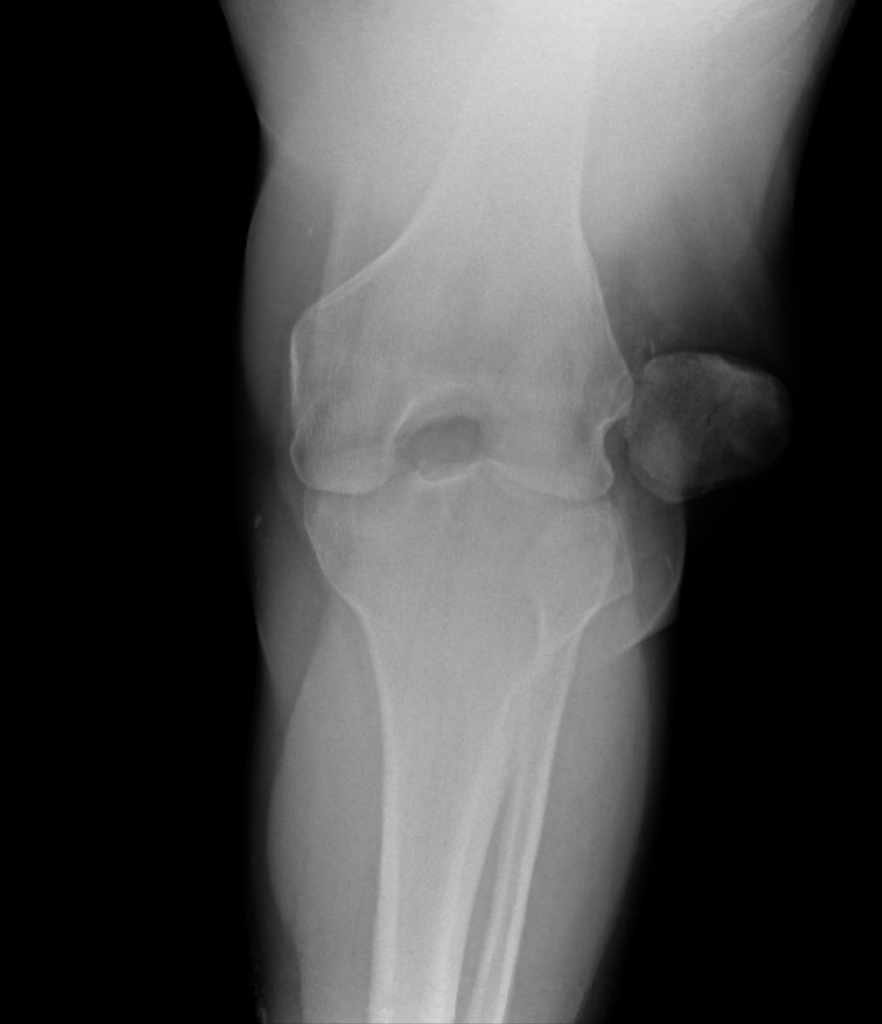

What’s the diagnosis? Gepost op 31 oktober 202027 oktober 2020 door netwerkvsseh What’s the diagnosis? By Dr. Sandhya Ashokumar @emdaily.cooperhealth.org Dit delen: Delen op X (Opent in een nieuw venster) X Share op Facebook (Opent in een nieuw venster) Facebook Delen op LinkedIn (Opent in een nieuw venster) LinkedIn E-mail een link naar een vriend (Opent in een nieuw venster) E-mail Afdrukken (Opent in een nieuw venster) Print Vind-ik-leuk Aan het laden... Gerelateerd